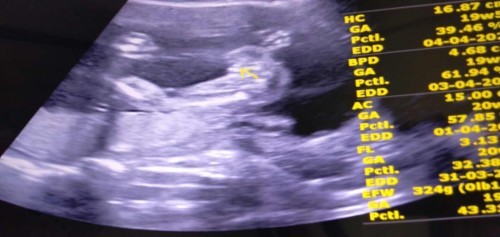

สอบถามแม่ๆหน่อยค่ะ เมื่อวานช่วงเช้าไปซาวน์ที่โรงบาลมา แต่หมอบอกว่าน้องยังเล็กอยู่ ยังบอกไม่ได้ ตอนเย็นคุณพ่ออยากรู้ เลยไปซาวน์ที่คลีนิคสูตินารีมาค่ะ บอกได้ผู้หญิง 90% เพราะเห็นกลีบชัดมาก คุณพ่อก็ดีใจไปเรียบร้อยแล้วค่ะ แต่มีคนบอกว่าคิดว่าผู้ชาย หมอดูผิดรึเปล่า ไม่รู้ว่าเค้าพูดเล่นพูดจริงค่ะ😂😂 กลัวคุณพ่อเค้าดีใจเก้อ ท้องแรกเราดูไม่เป็นค่ะ น้อง 20+4 ค่ะ (5เดือน) #ขอบคุณสำหรับคำตอบค่ะ